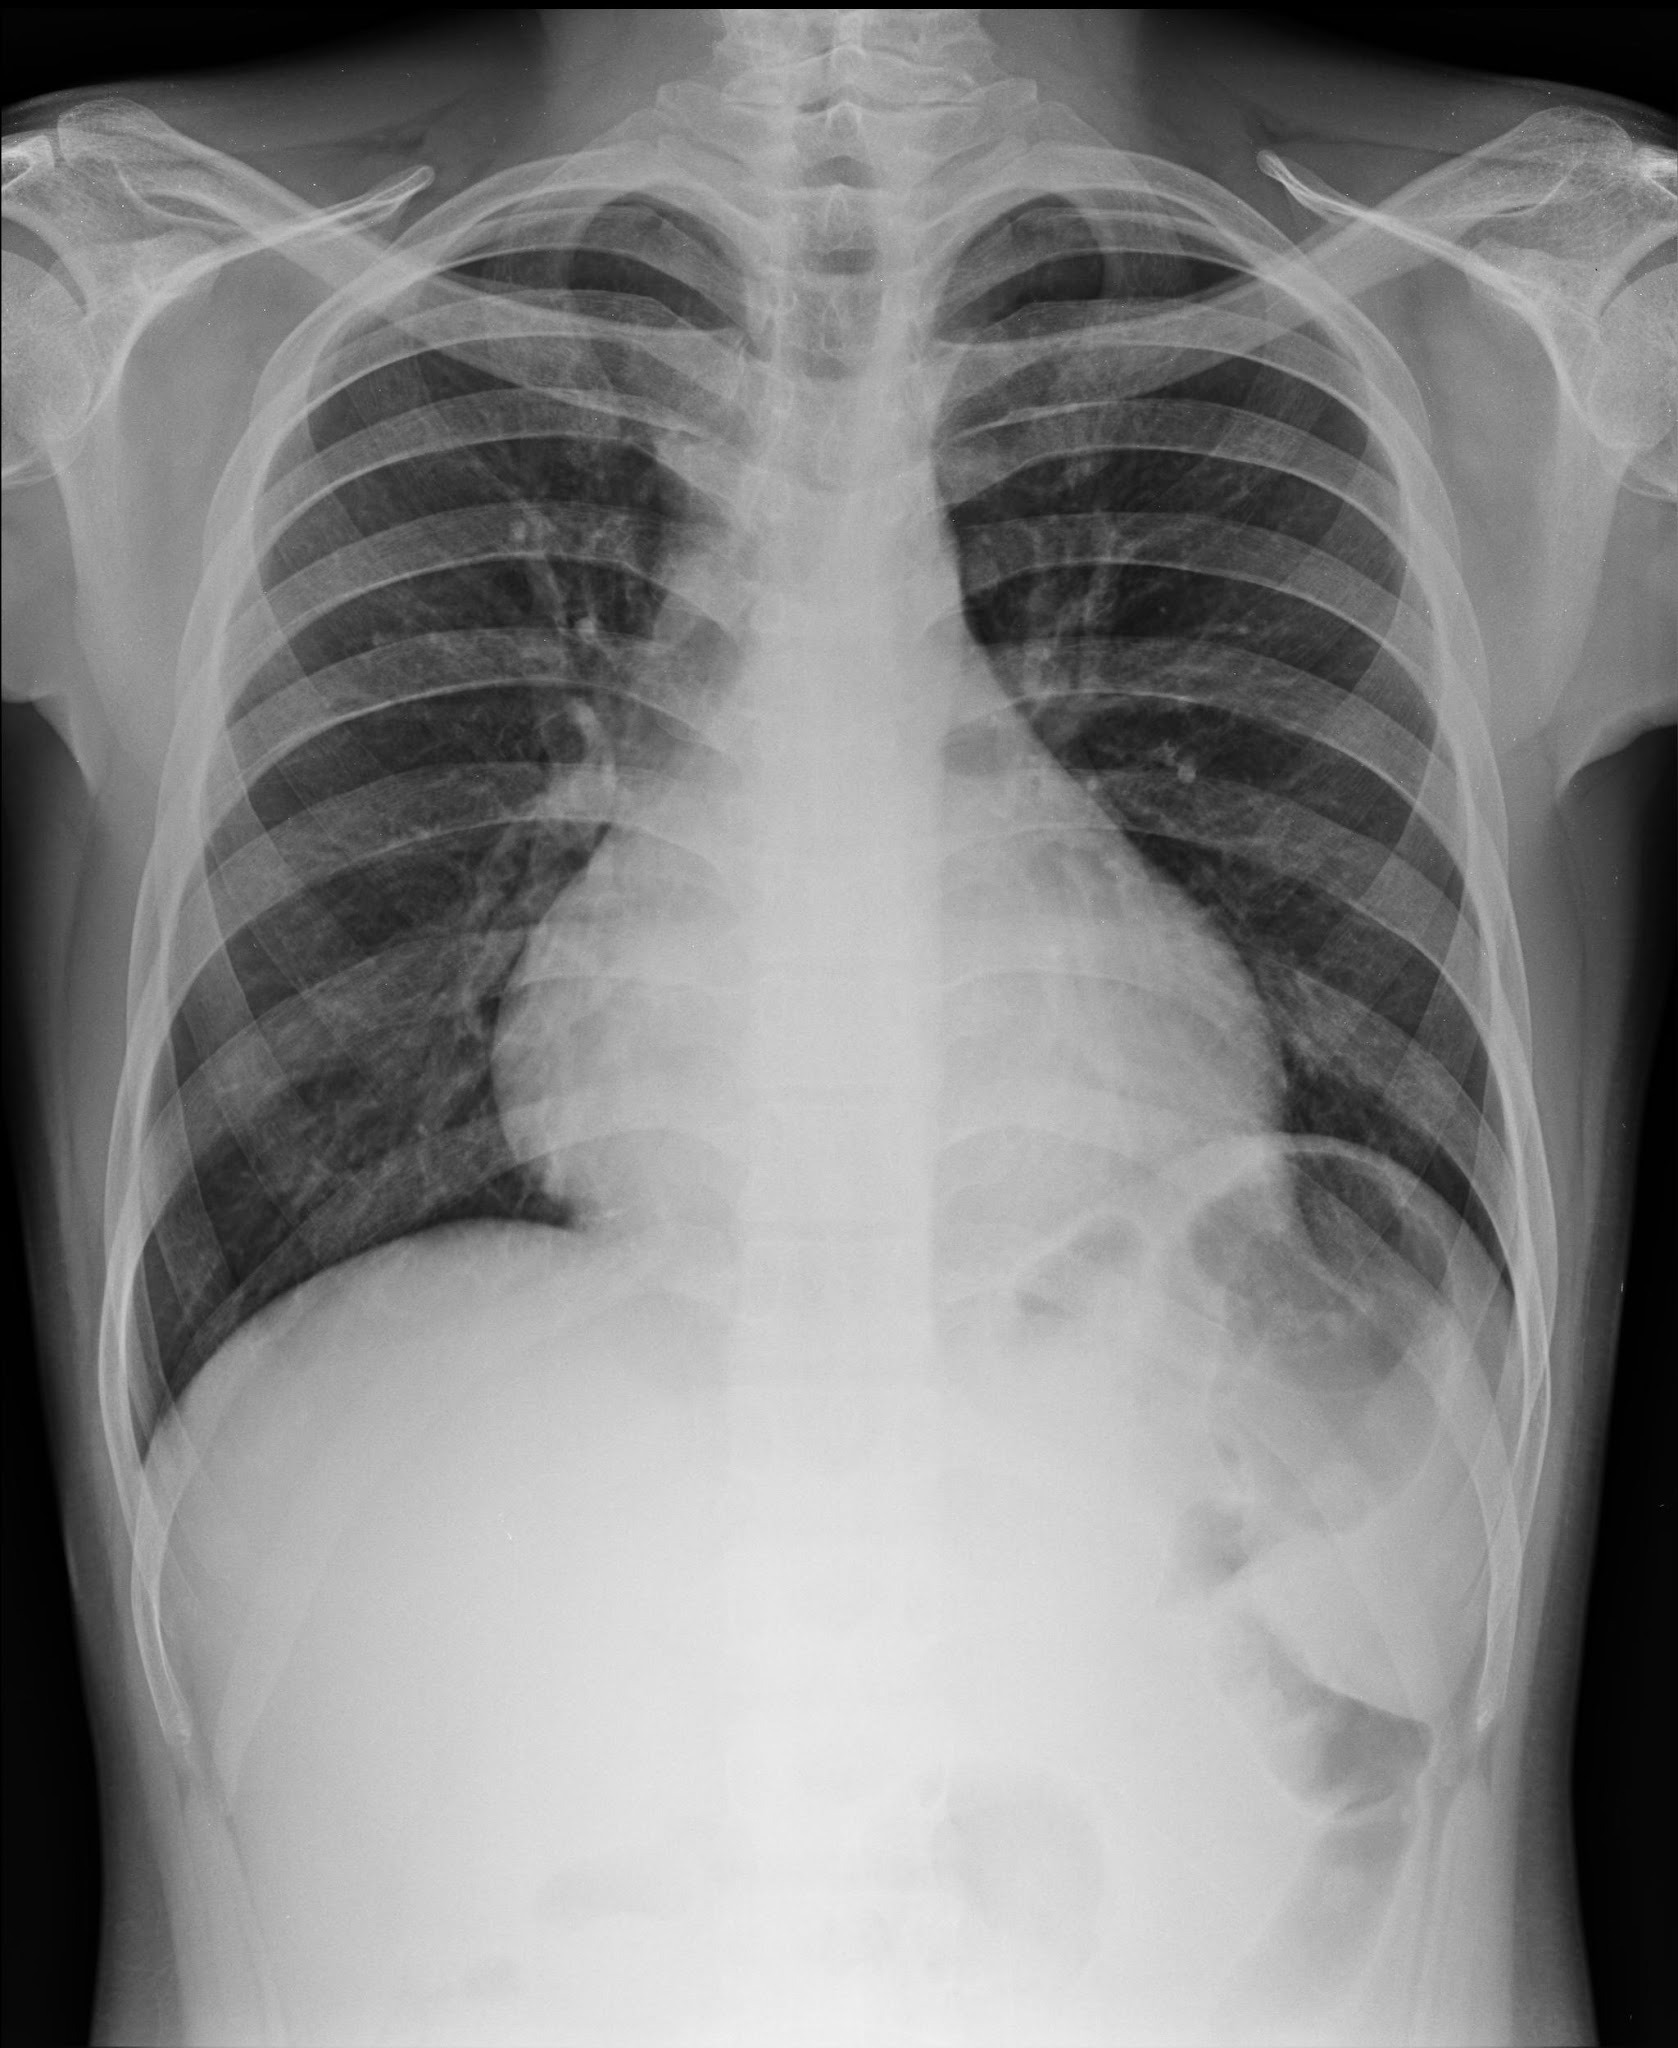

Frontal and lateral views of the chest demonstrate airspace disease on the lateral film (B) in the right lower lobe (white arrow) that may not be immediately apparent on the frontal film (you can see the pneumonia in the right lower lobe in [A] [black arrow]).

In this case, a right lower lobe pneumonia superimposed on the lower spine on the lateral view makes the spine appear “whiter” (more dense) just above the diaphragm. This is called the spine sign.